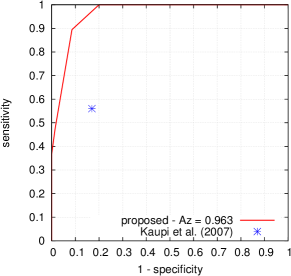

Given a target lesion type, Kauppi et al. (2007) proposed a standardized procedure to evaluate the performance of a lesion detector, at the image level, in the DiaretDB1 dataset. In this purpose, one probability map was constructed per image: this map was obtained by averaging, at the pixel level, confidences from all four experts for the target lesion type. If and only if this map contains at least one pixel with an average confidence level above 75 , then the image is considered to contain the target lesion. Based on this criterion, a receiver-operating characteristic (ROC) curve can be constructed for the lesion detector.

FROC curves are reported in Fig. 6 for ‘net B’; areas under the limited FROC curve for all three ConvNets are summarized in Table 3. It appears that the number of false alarms is rather large, particularly in the case of microaneurysm detection. The reason is that human experts primarily segmented the most obvious lesions, while screening algorithms need to focus on the most subtle lesions as well. In other words, many true lesions are counted as false alarms. Of course, this comment also applies to competing automatic solutions. To show the value of our detections, the proposed solution was compared in Fig. 7 to results reported in the literature, following the DiaretDB1 standardized procedure (see section 5.3.2). Most authors reported a single (sensitivity, specificity) pair: this is what we reported in Fig. 7. Some authors reported ROC curves; in that case, we also reported a single (sensitivity, specificity) pair: the one closest to the (sensitivity = 1, specificity = 1) coordinate. Note that all competing solutions (Kauppi et al., 2007; Yang et al., 2013; Franklin and Rajan, 2014; Kumar et al., 2014; Bharali et al., 2015; Mane et al., 2015; Dai et al., 2016) are trained at the lesion level, while ours is trained (in Kaggle-train) at the image level.

Three ConvNets were trained to detect referable DR in the Kaggle-train dataset, using the proposed heatmap optimization procedure. Then, we evaluated how well those ConvNets could detect lesions in the DiaretDB1 dataset, without retraining them. For lesion detection at the image level, they outperformed previous algorithms, which were explicitly trained to detect the target lesions, with pixel-level supervision (see Fig. 7). This superiority was observed for all lesions or groups of lesions, with the exception of ‘red lesions’. Experiments were also performed at the lesion level: for all lesion types, the proposed algorithm was found to outperform recent heatmap generation algorithms (see Table 3). As illustrated in two examples (see Fig. 9 and 10), the produced heatmaps are of very good quality. In particular, the false alarms detected on the vessels, in the vicinity of true lesions in the unoptimized heatmaps ( maps), are strongly reduced with sparsity maximization (, , ). These experiments validate the relevance of image-level supervision for lesion detectors, but stress the need to optimize the heatmaps, as proposed in this paper. Note that detection performance is not affected much by image quality: very good detections are produced in the blurry image obtained with a low-cost, handheld retinograph (see Fig. 10). This is a very important feature, which opens the way to automated mobile screening. However, it can be observed that the ‘AlexNet’ architecture, which achieves moderate DR detection results, also achieves poor detection results at the lesion level, even after heatmap optimization (see Table 3): to ensure good detection performance at the lesion level, the proposed optimization framework should be applied to ConvNet architectures that achieve good image-level performance.